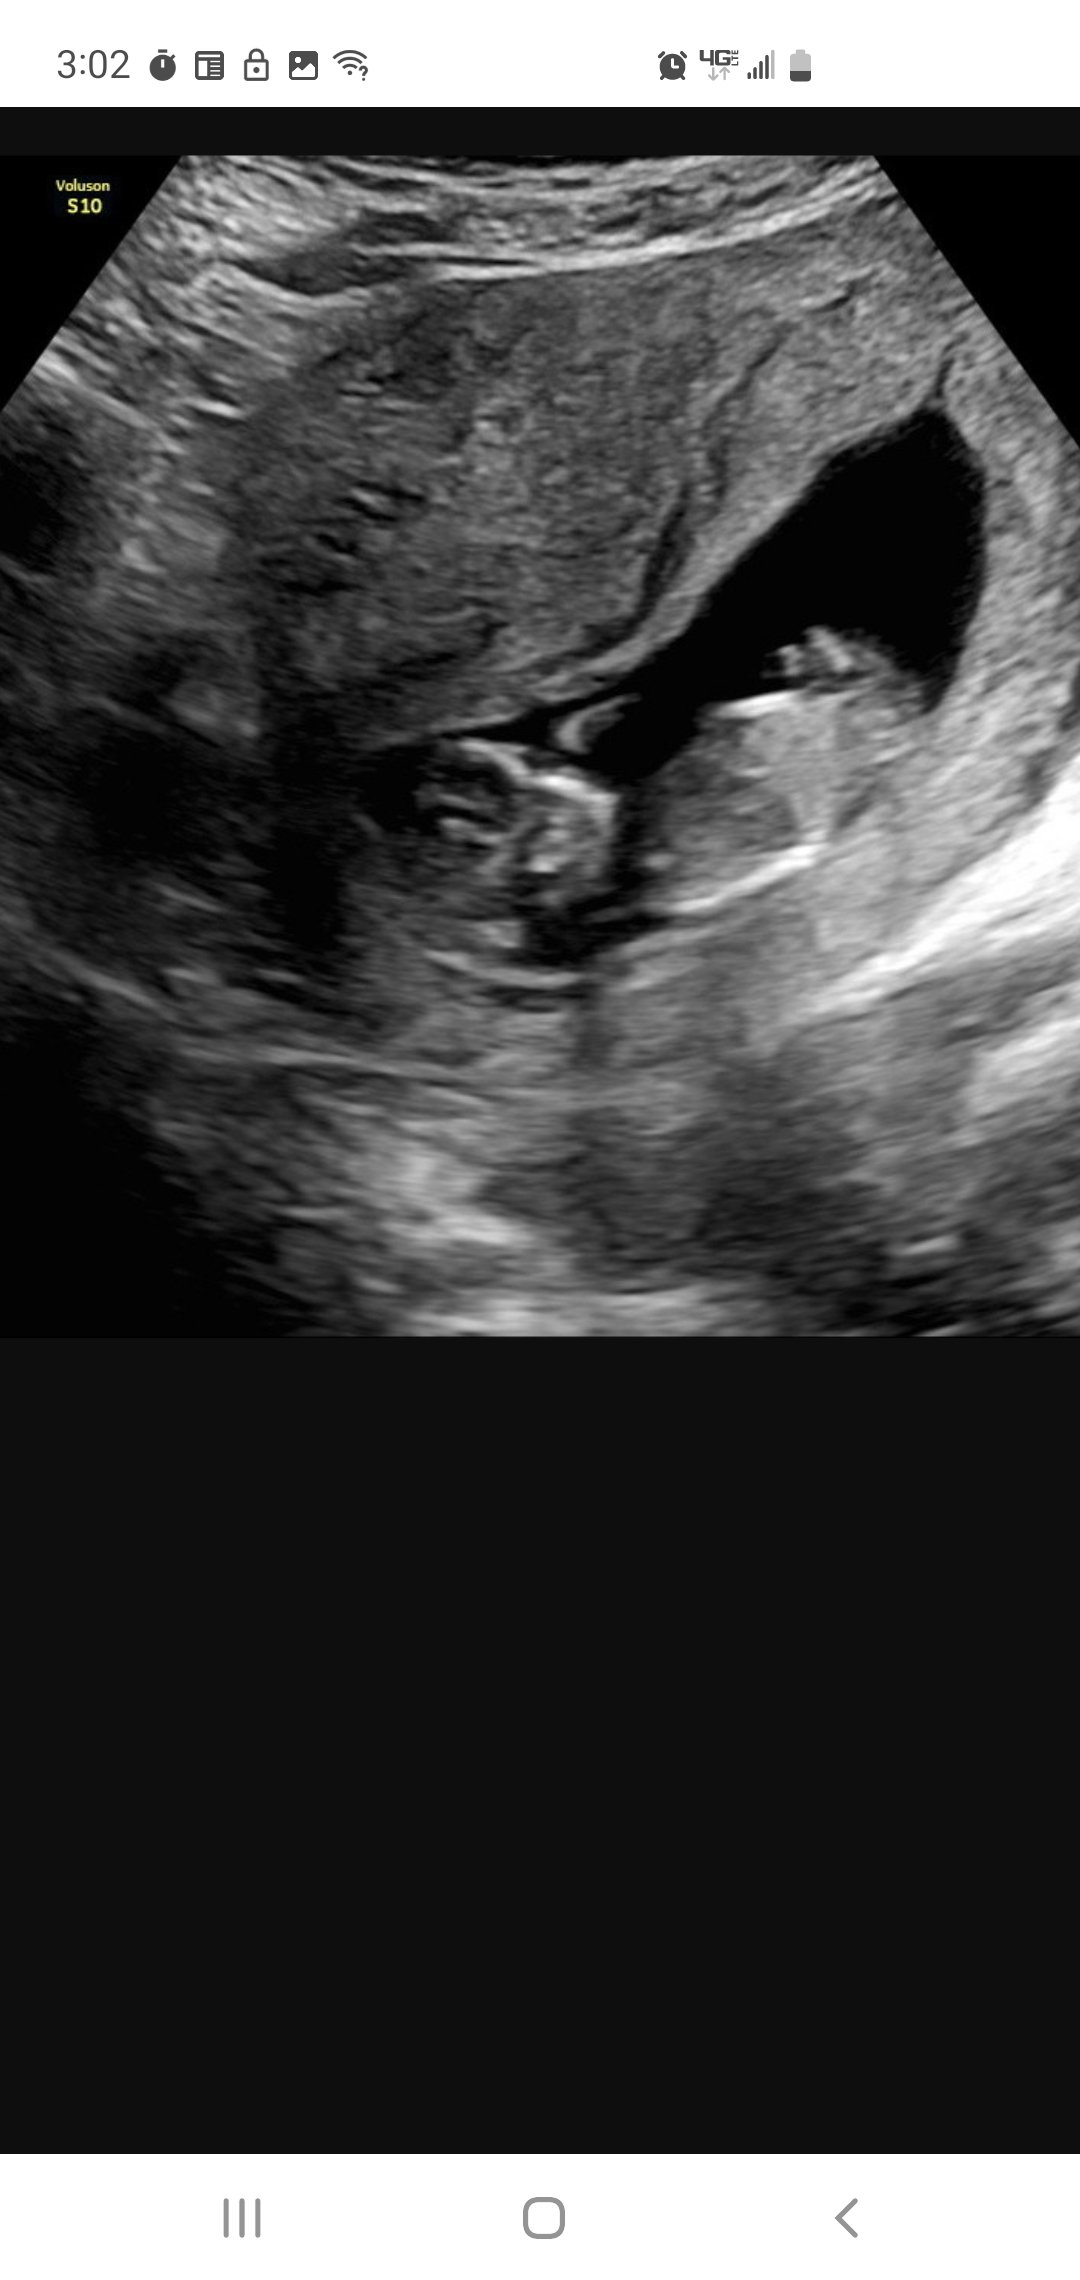

It's really real. They adjusted my due date by 1 day so I guess I'm now 9 weeks on the dot and due 11/2. Strong heartbeat at 178 bpm. Had a fun appointment explaining to all the new doctors that this is my 4th total pregnancy (2 viable, 1 mc) and we already have 4 kids. It took them a minute. 🤣